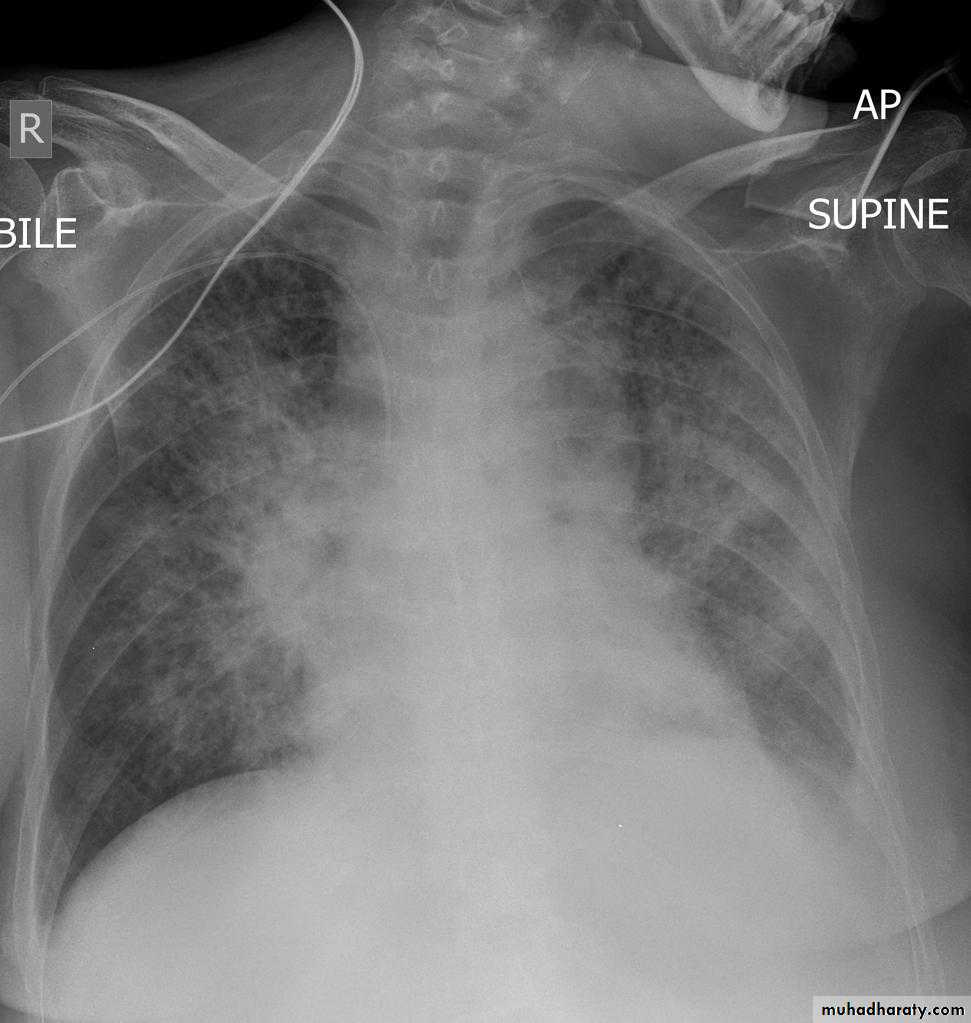

Radiographic features

Chest radiograph

With left sided congestive cardiac failure, the features are that of pulmonary edema which includes:

central pulmonary venous congestion ( prominent hilum )

cephalisation of pulmonary veins ( upper lobe pulmonary venous diversion )

pulmonary interstitial oedema

pulmonary alveolar oedema

Cardiomegaly

Pleural effusion

radiograph include if pressure > 25 mmHg the findings of :

cardiac size/cardio-thoracic ratio: useful for assessing for an underlying cardiogenic cause or associationbat wing pulmonary opacities

presence of peri-bronchial cuffing

septal lines: Kerley lines become more prominent

pleural effusions

pulmonary venous engorgement/pulmonary blood flow distributionupper lobe pulmonary venous diversion

Alveolar pulmonary edema